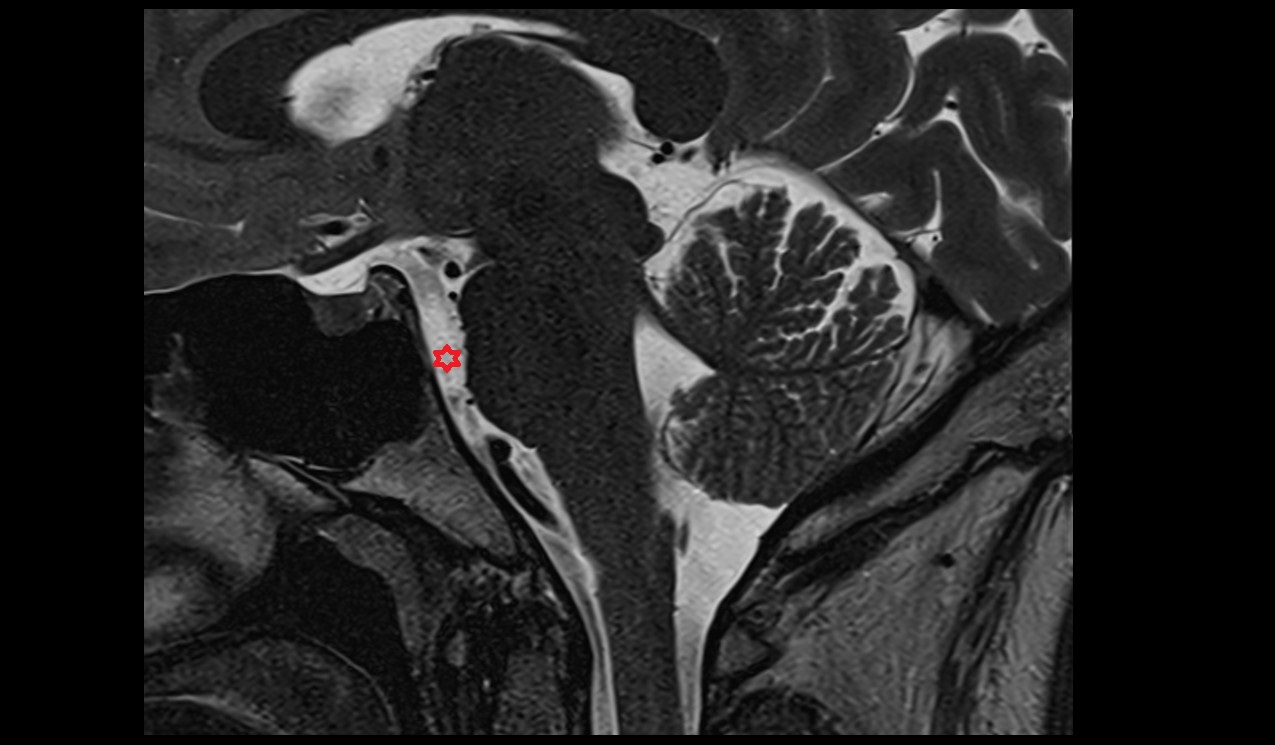

- Uterus

- Body of uterus

- Fundus of uterus

- Cervix of uterus

- Isthmus of uterus

- Endometrium of uterus

- Myometrium of uterus

- Perimetrium of uterus

- Junctional zone of uterus